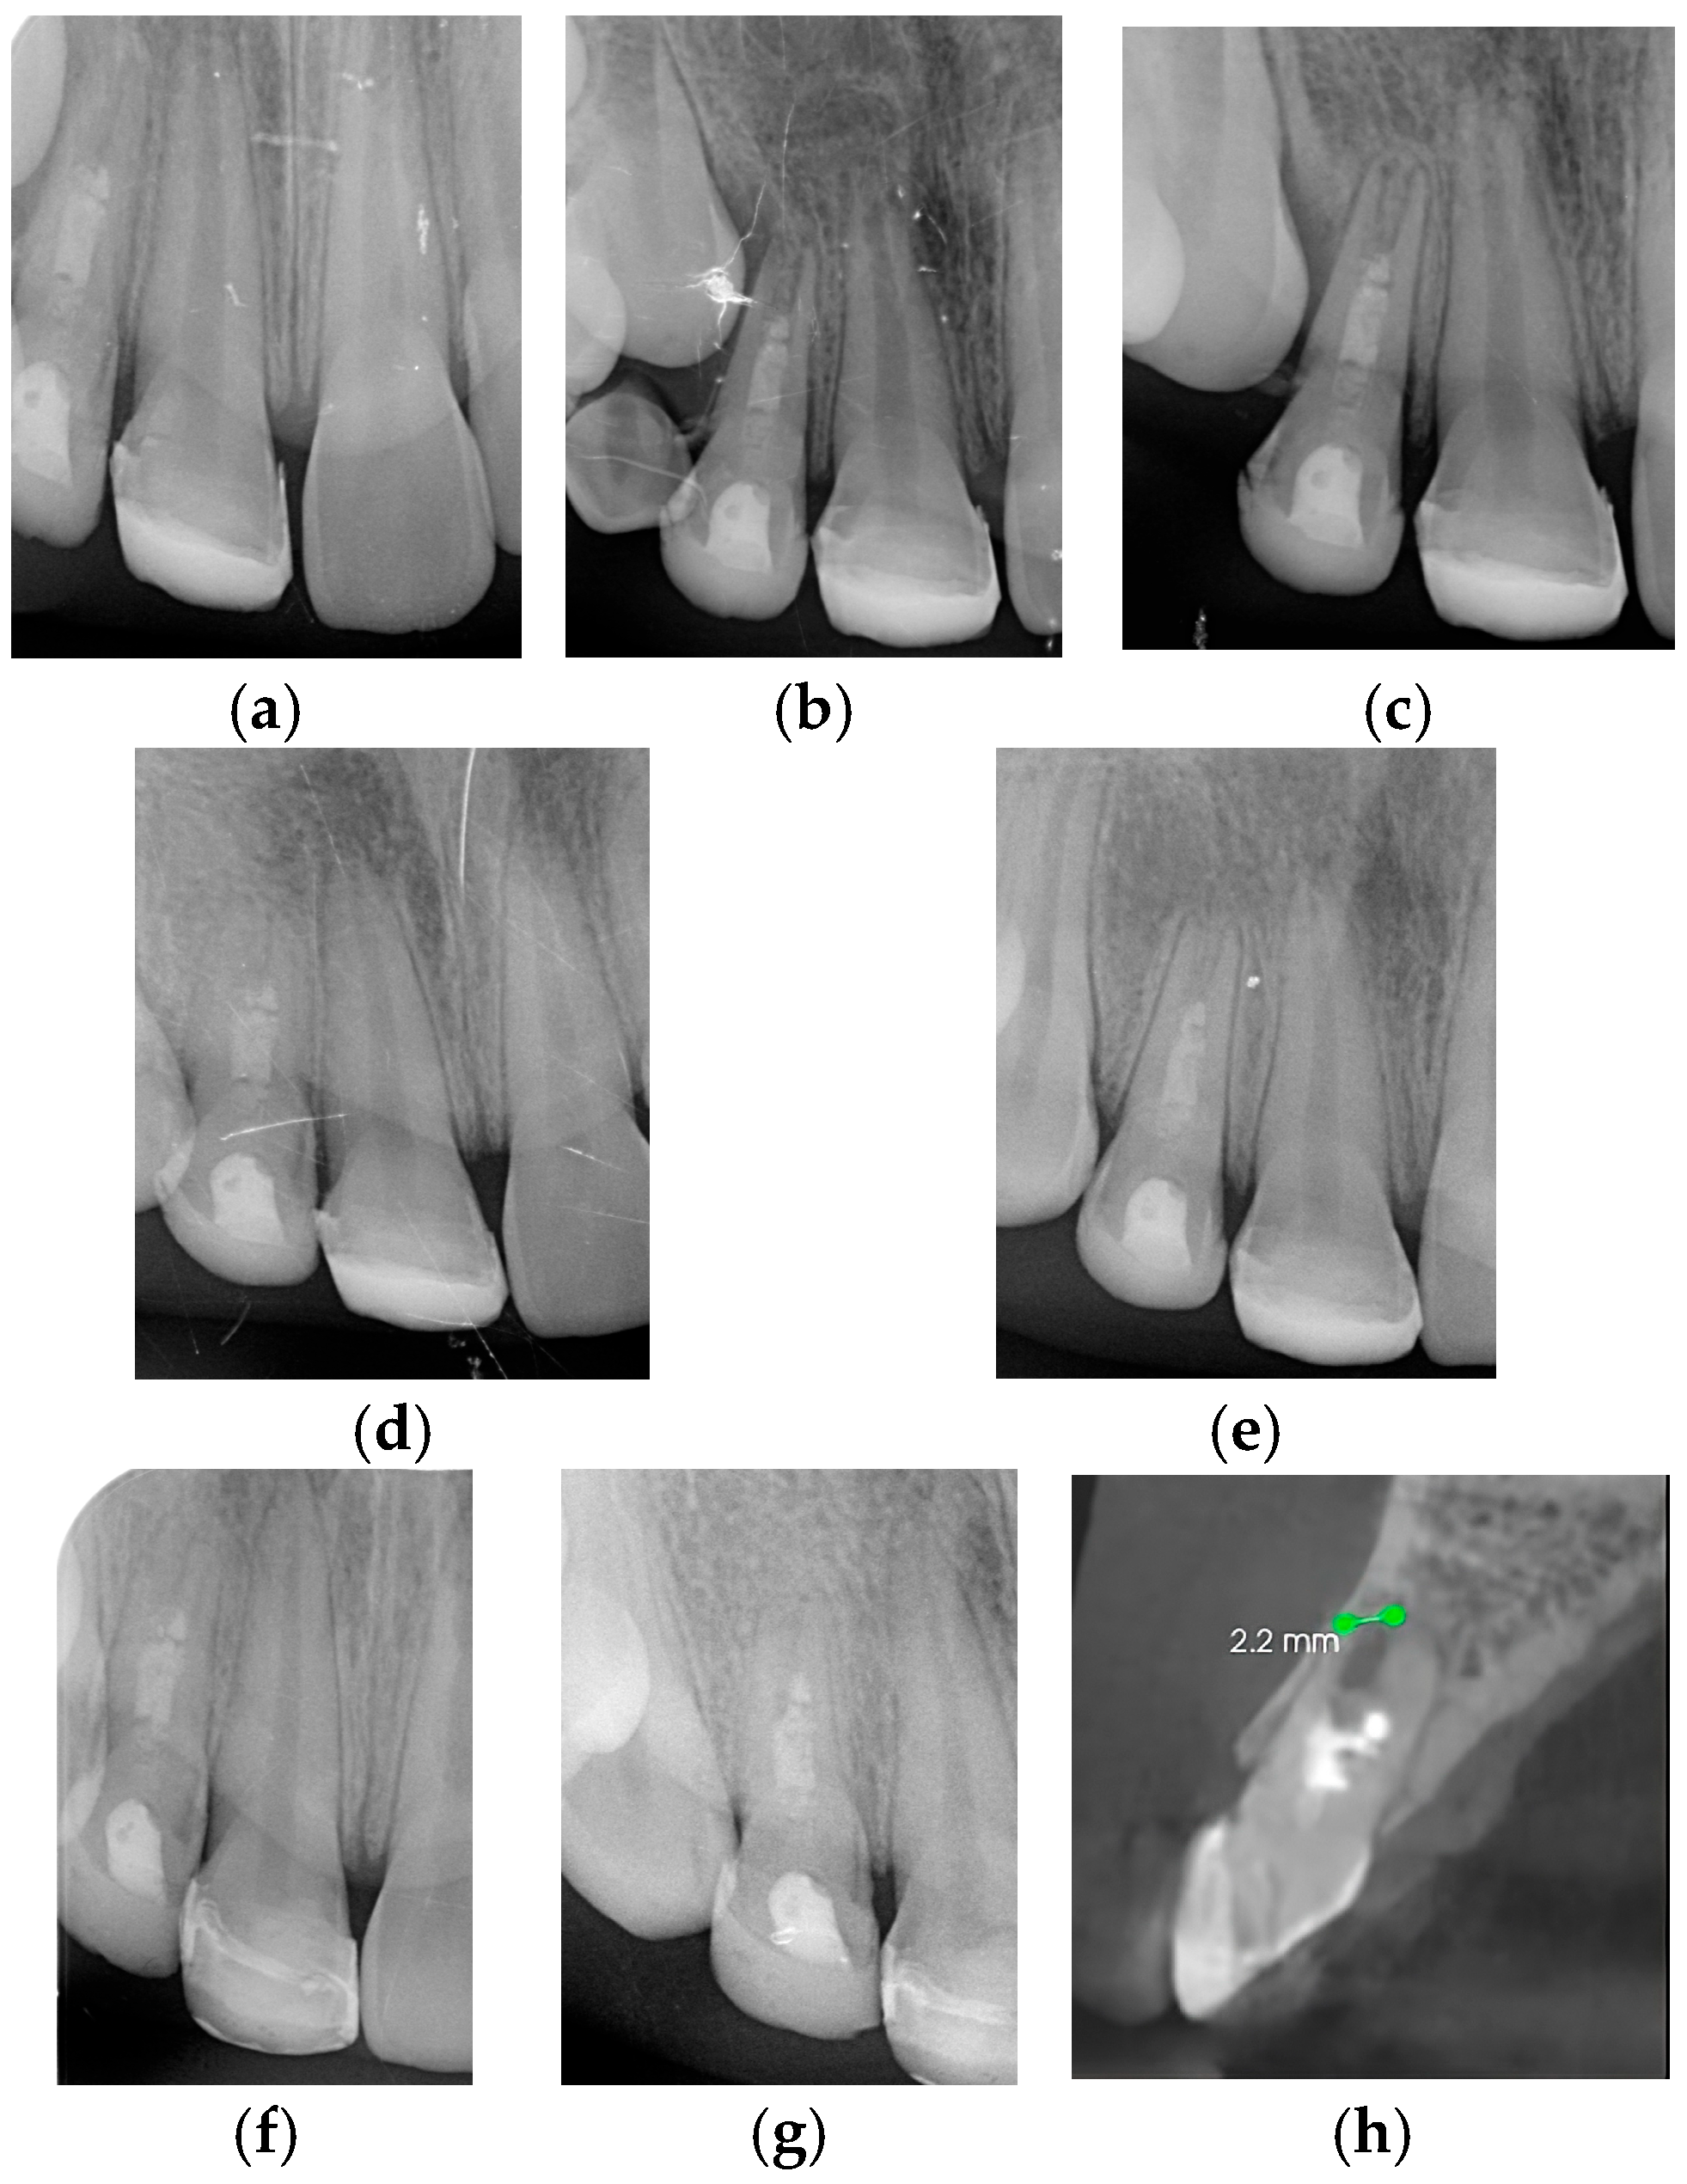

| Case 1 | 12 | 17% EDTA NaOCl | TAP | MTA | 3.7 mm | 2.2 mm | Calcified apical barrier |

| Case 2 | 11/21 | 17% EDTA NaOCl | Ca(OH)2 | BIODENTINE® | 3.1 mm/2.8 mm | 2.3 mm/2 mm | Calcified apical barrier |